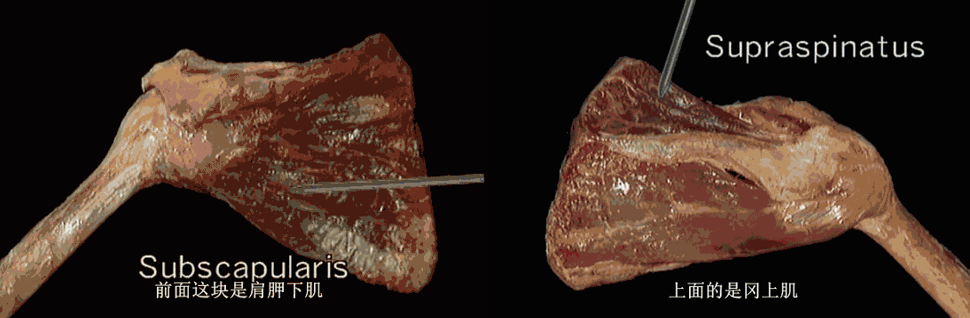

肩袖是覆盖于肩关节前、上、后方之肩胛下肌、冈上肌、冈下肌、小圆肌等肌腱组织的总称。位于肩峰和三角肌下方,与关节囊紧密相连。

冈上肌和肩胛下肌腱融合成一个鞘状结构,在肱二头肌沟入口处环绕肱二头肌腱。鞘的顶层是由冈上肌腱组成,底层是由肩胛下肌腱组成。这种关系与肩胛下肌腱撕裂常并发二头肌损伤有相关性。